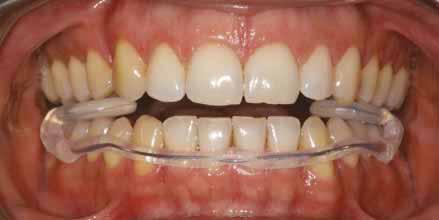

A fogszabályozás aktív fázisa után minden kezelésnél a retenció, a passzív helyben tartó fázis a kezelési eredmény megtartására rendkívül fontos!

Az Essix retainerek, az egy fogívre kiterjedő mélyhúzott sínek, valamint a felső és alsó frontfogakra orálisan ragasztott fix retainerek mellett, a harapás sagittális rögzítésében elengedhetetlen szerepe van az ún. Pitts Izom Tréning Splint-nek, amelybe a páciens élharapásban összeharap, így az megakadályozza az alsó fogsor visszamozdulását a disztálharapásos helyzetbe (13. kép)